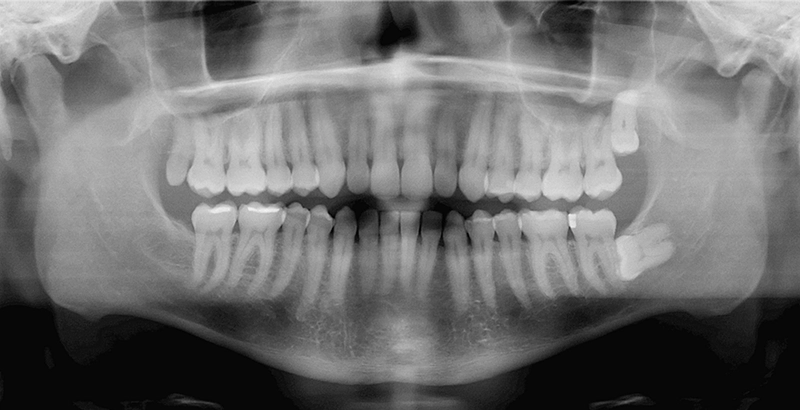

Routine dental assessments play an important role in identifying wisdom tooth issues before they become more complex. Dentists use clinical examinations and diagnostic imaging to assess the position, development, and impact of wisdom teeth, including problems that are not visible during a standard check-up.